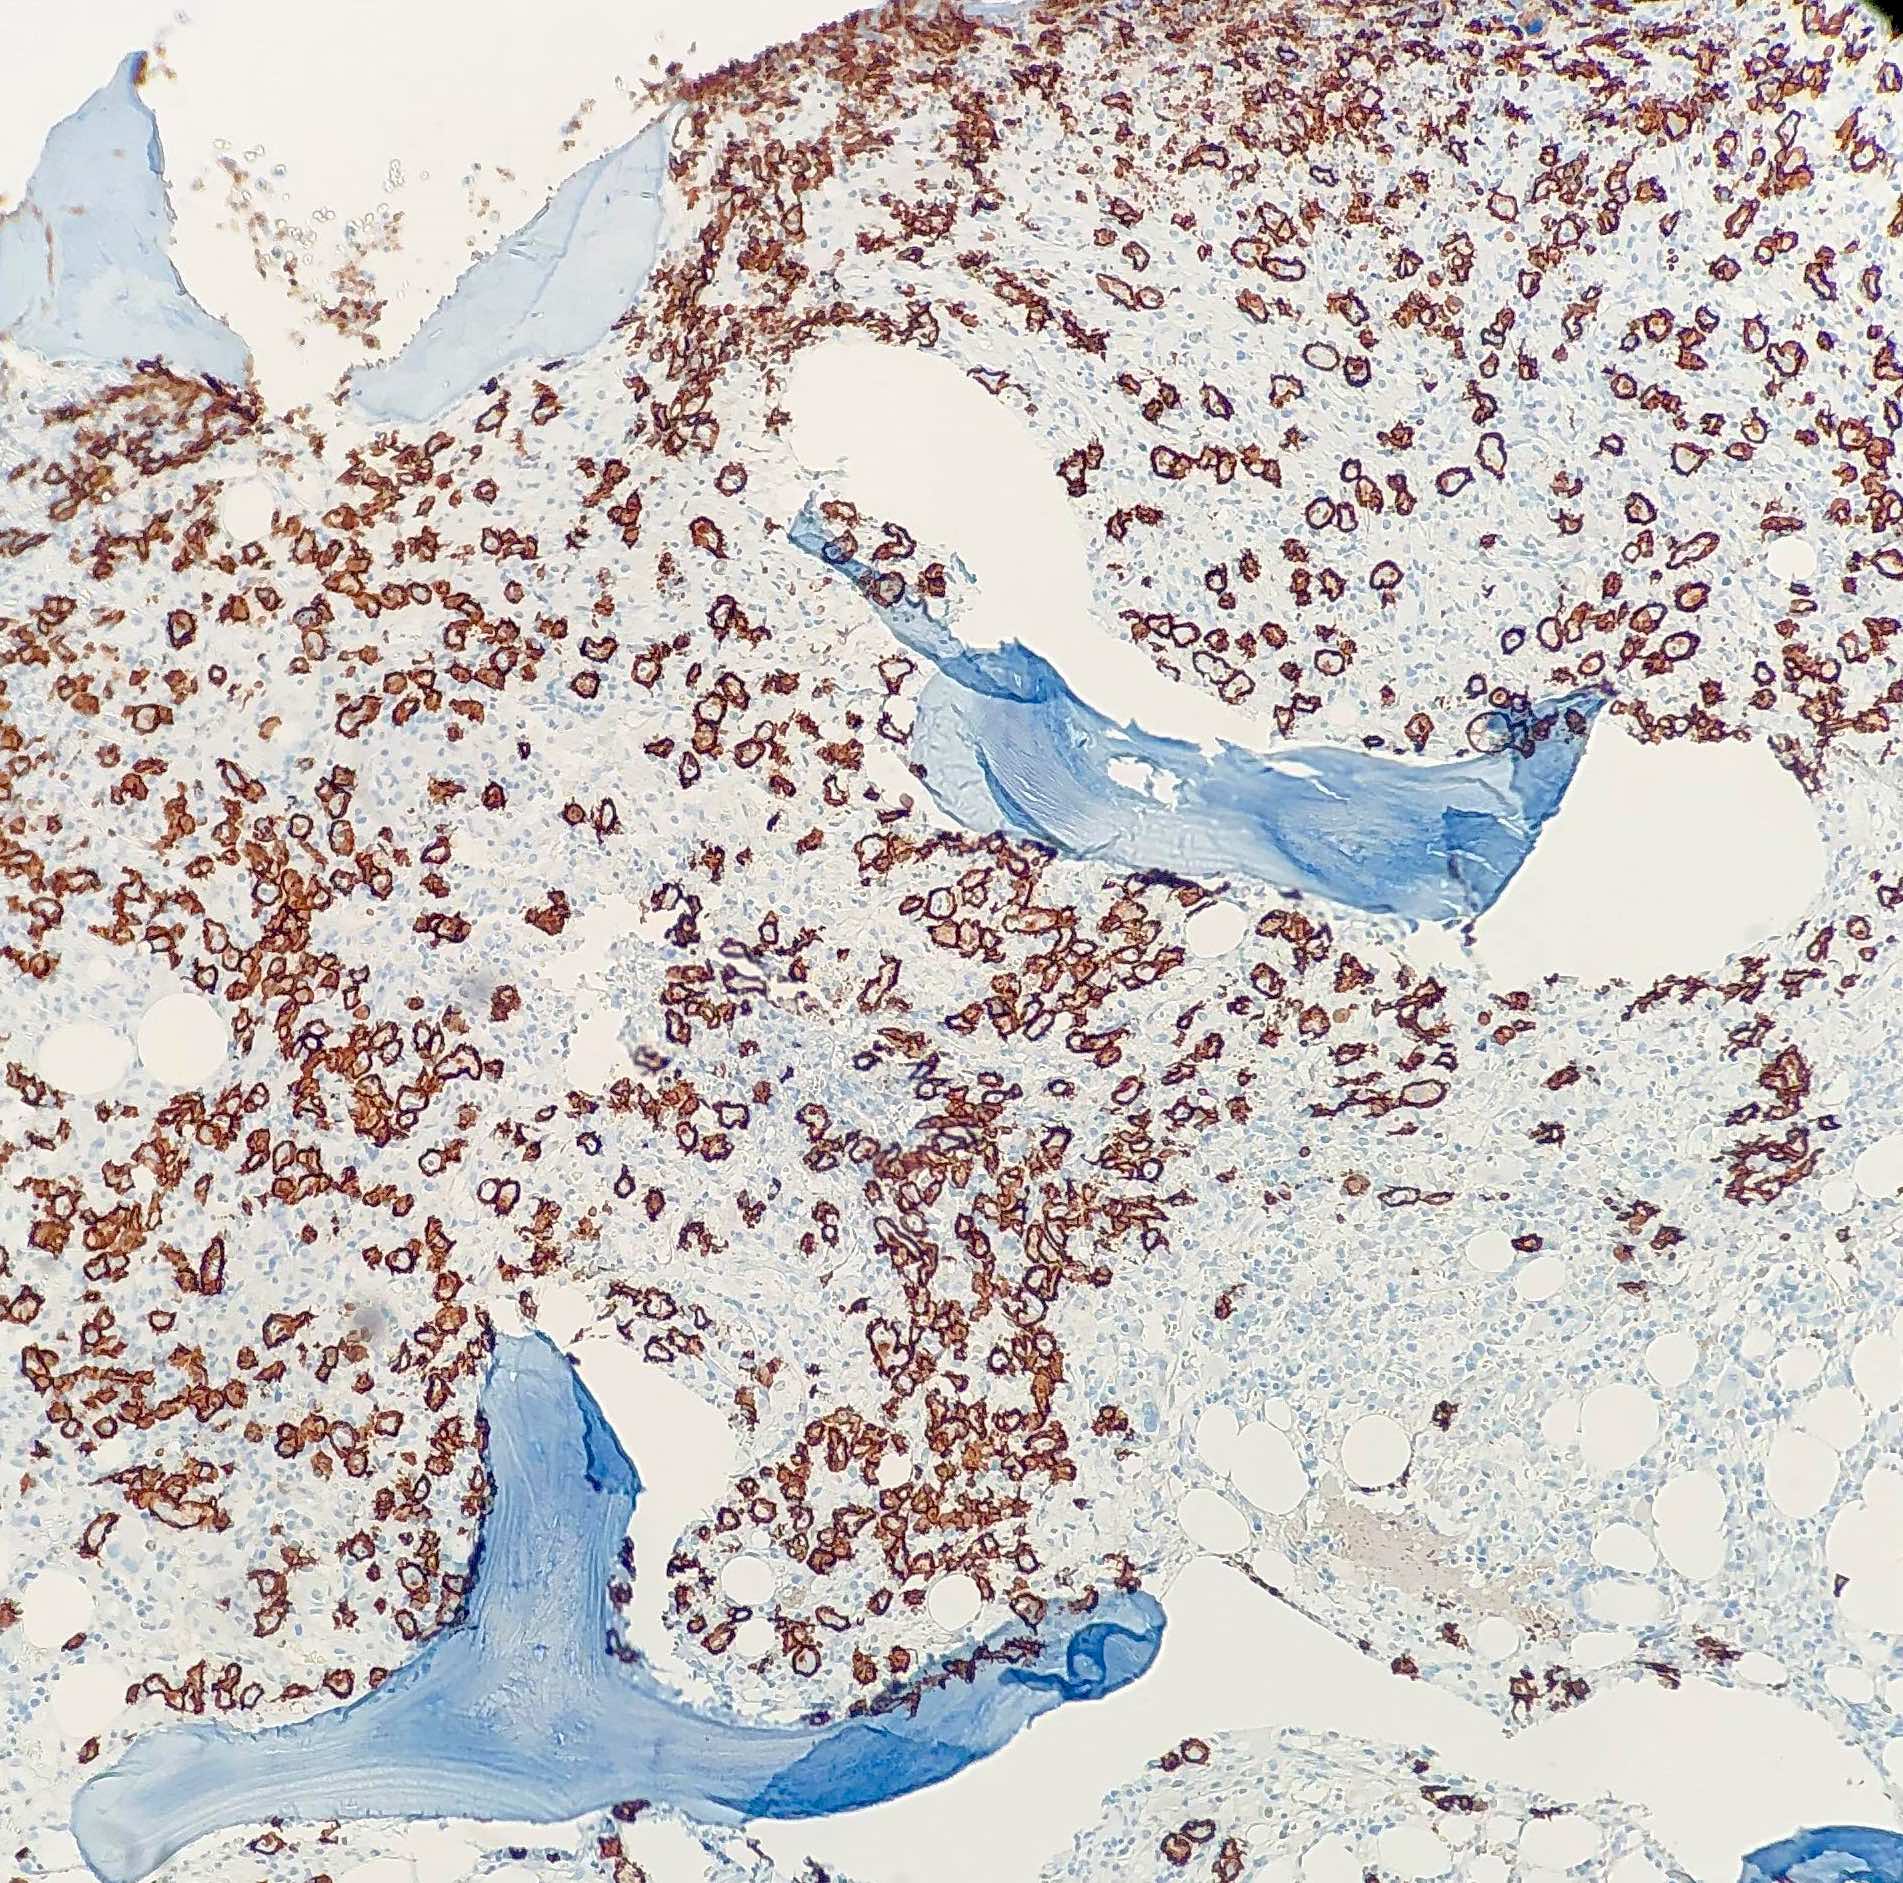

Positive stains

- B cell markers (CD20, PAX5, CD79a, CD19, CD22)

- Cell of origin subtyping: CD10 (30 - 50%), MUM1 (35 - 65%), BCL6 (60 - 90%)

- Evaluation of double expresser / possible double hit status: BCL2 (47 - 84%), MYC

- Ki67 (high)

- CD30 (14%), associated with anaplastic morphology (Blood 2013;121:2715)

- CD5 (12%) (Eur J Haematol 2017;98:415)

- Cell of origin subtype prediction by IHC using the Hans algorithm (positivity defined as staining in ≥ 30% of cells) (Blood 2004;103:275):

- Germinal center B cell (GCB) subtype: CD10+ or CD10- / BCL6+ / MUM1-

- Non-GCB subtype (classifier that encompasses ABC subtype and unclassifiable cases by GEP): CD10- / BCL6- or CD10- / BCL6+ / MUM1+

- Double expresser status (30% of DLBCL, NOS):

- Positive staining for BCL2 (> 50% tumor cells) and MYC (> 40% tumor cells) in the absence of underlying chromosomal rearrangements (double expresser) is associated with increased risk of CNS relapse and inferior survival (J Clin Oncol 2017;35:2515)

- If MYC and BCL2 rearrangements confirmed by FISH, classified as high grade B cell lymphoma with MYC and BCL2 rearrangements (also known as double hit DLBCL)